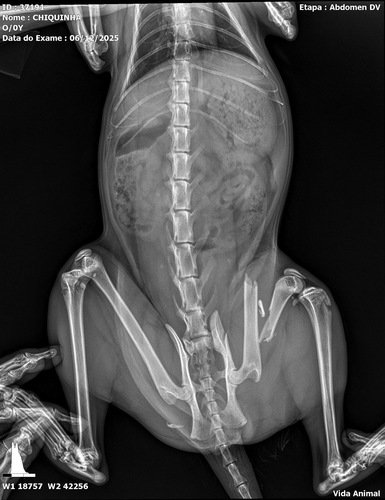

Chiquinha é uma gatinha muito querida que, infelizmente, foi atropelada e fraturou a pata. Para que ela volte a andar sem dor, é essencial realizar uma cirurgia para colocação de um pino no osso.

A consulta veterinária e o exame de raio-X já foram pagos, mas ainda falta arrecadar o valor do procedimento cirúrgico. Por isso criamos esta vaquinha solidária: cada doação nos aproxima do objetivo de garantir o melhor tratamento para a Chiquinha.